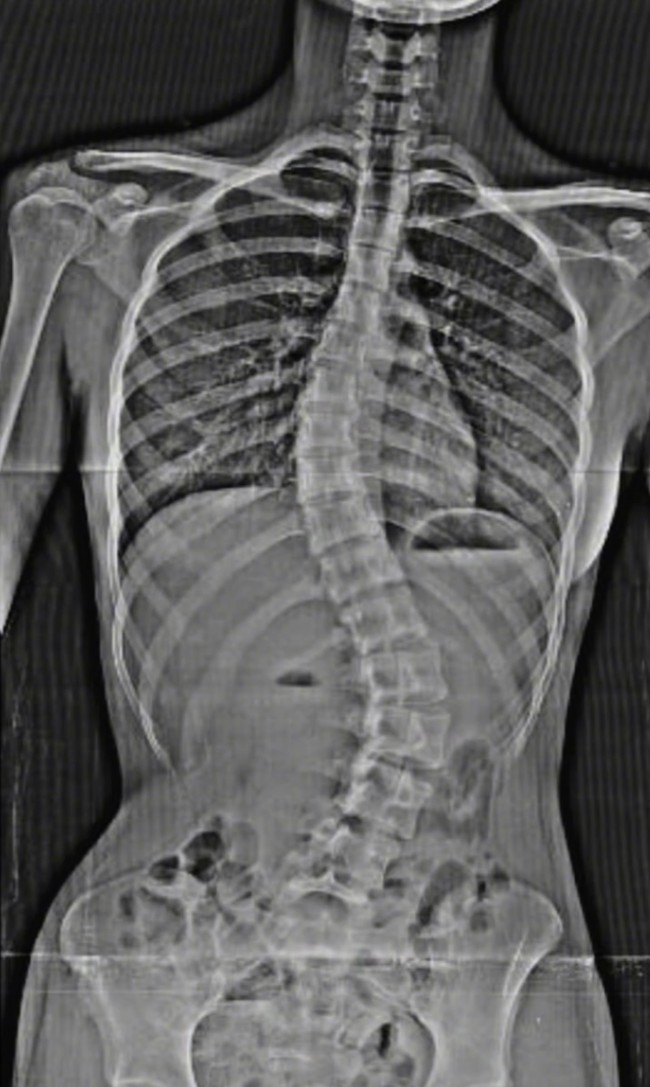

Jakarta - Putri angkat Deddy Corbuzier, Nada Tarina Putri beberapa waktu lalu menjalani operasi skoliosis. Melalui akun Instagram, Nada membagikan perjalanan operasinya.